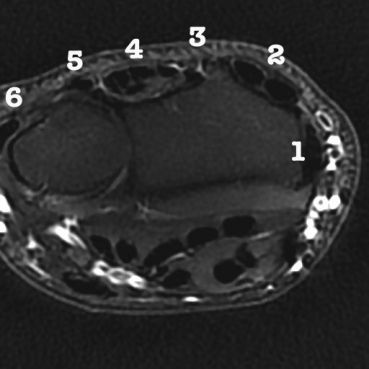

Le cloisonnement engendré par les expansions du rétinaculum des extenseurs crée une subdivision en 6 compartiments.

De dehors en dedans :

Compartiment 1 :

- long abducteur et court extenseur du 1er rayon (abductor pollicis longus et extensor pollicis brevis)

Compartiment 2 :

- radiaux (extensor carpi radialis brevis et longus)

Compartiment 3 :

- long extenseur du 1er rayon (extensor pollicis longus)

- 6 à 7 cm de long

- la gaine peut s'étendre jusqu'au trapéze, voire la base du métacarpien

Compartiment 4 :

- contient l'extenseur commun des doigts et l'extenseur propre du 2éme rayon (extensor communis et extensor indicis proprius)

- 5 à 6 cm de long

Compartiment 5 :

- extenseur propre du 5éme rayon (extensor quinti proprius)

- parfois communication avec l'articulation radio-cubitale inférieure

Compartiment 6 :

- cubital postérieur

- sa gaine mesure 4 à 5 cm de long